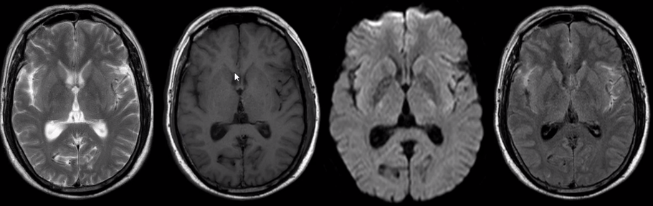

2.脑出血影像学表现

信号特征复杂,与血管内红细胞的完整性及血红蛋白的演变有关。

(1)超急性期 CT 高密度;T1WI 呈等或略低信号,T2WI 呈高信号。

(上下滑动查看全部图片)

(2)急性期 CT 高密度;T1WI 呈等信号,T2WI 呈低信号。

(3)亚急性期 CT 密度逐渐减低与脑实质相仿 1w、t2 呈高信号。

(4)慢性期 CT 囊性病灶,可见钙化;T2WI 高信号血肿周围被低信号含铁血黄素包饶。